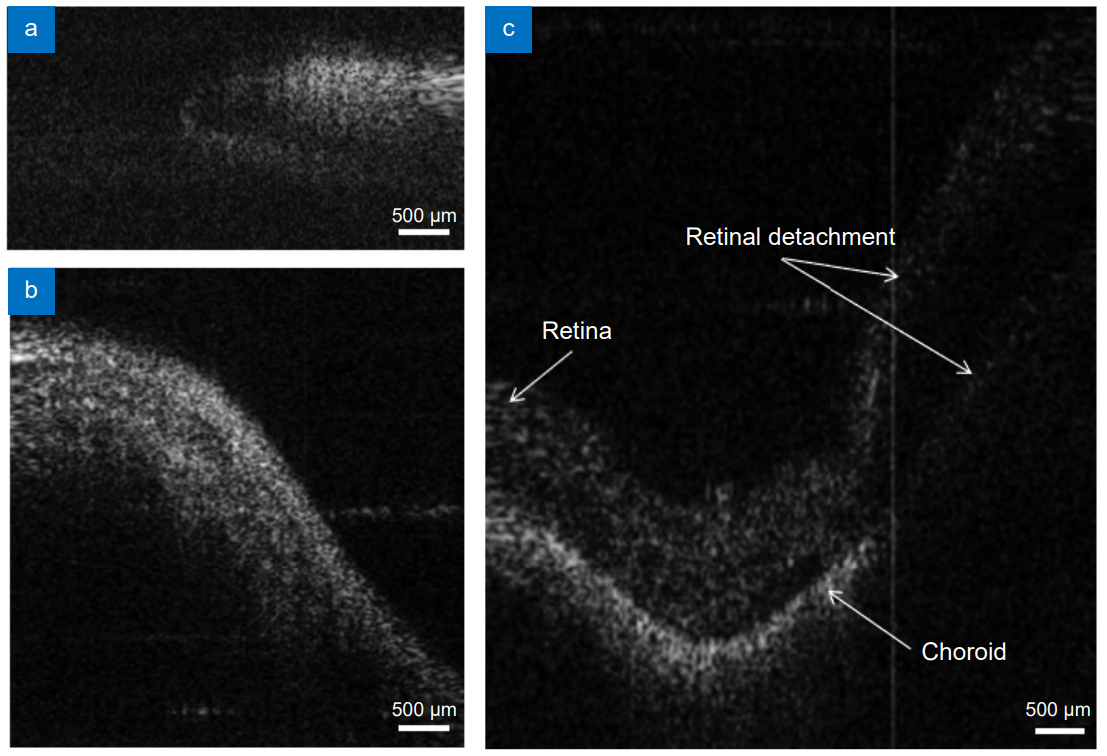

为验证该探头在眼科的应用可行性,将内窥探头从离体猪眼睫状体平坦部切口伸入内部,可清晰、完整的获取猪眼视网膜图像,并观测到视网膜表层、脉络膜等结构以及视网膜脱落现象,如图3所示。这表明该探头未来应用于眼科临床手术的潜力。该工作以“大视场内窥光学相干层析成像探头的光学设计与应用”为题作为封面文章发表在《光电工程》2025年第6期。

图3 内窥探头拍摄的离体猪眼图像。(a)虹膜;(b)巩膜;(c)视网膜。